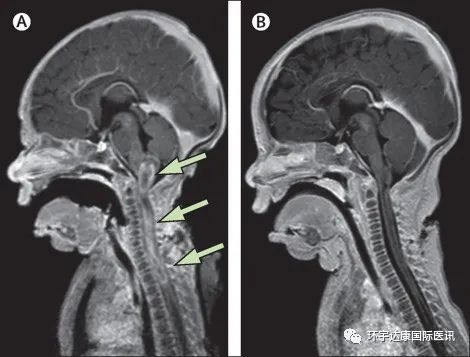

一名刚出生的婴儿脑和脊柱的增强核磁显示髓内病变从延髓向下延伸到上胸段脊髓出现异常,确诊为 IV 级先天性脊髓胶质母细胞瘤。手术切除部分肿瘤的同时,医生也把组织标本送到基因检测公司进行了全基因组测序,结果显示存在特定的 NTRK融合。

就在接受了诱导化疗和低剂量 VITRAKVI(拉罗替尼)治疗后一周,这名婴儿的脊柱肿瘤就已经出现了肉眼可见的缩小;第二周,医生就加大了剂量,开始100 mg/m 2的全剂量进行治疗,这时病灶已经显着减小,她的四肢瘫痪也出现了明显改善。

令医生们难以置信的是,VITRAKVI(拉罗替尼)联合化疗治疗了8周后,肿瘤已完全消退,影像学显示已经没有任何病灶!

事情一直在往好的方向发展。治疗后 17 个月,这个曾经命悬一线的幸运儿已经开始开始爬行并学着走路了!截至文章发表时,她还在接受VITRAKVI(拉罗替尼)的治疗,没有任何证据表明肿瘤进展和复发!